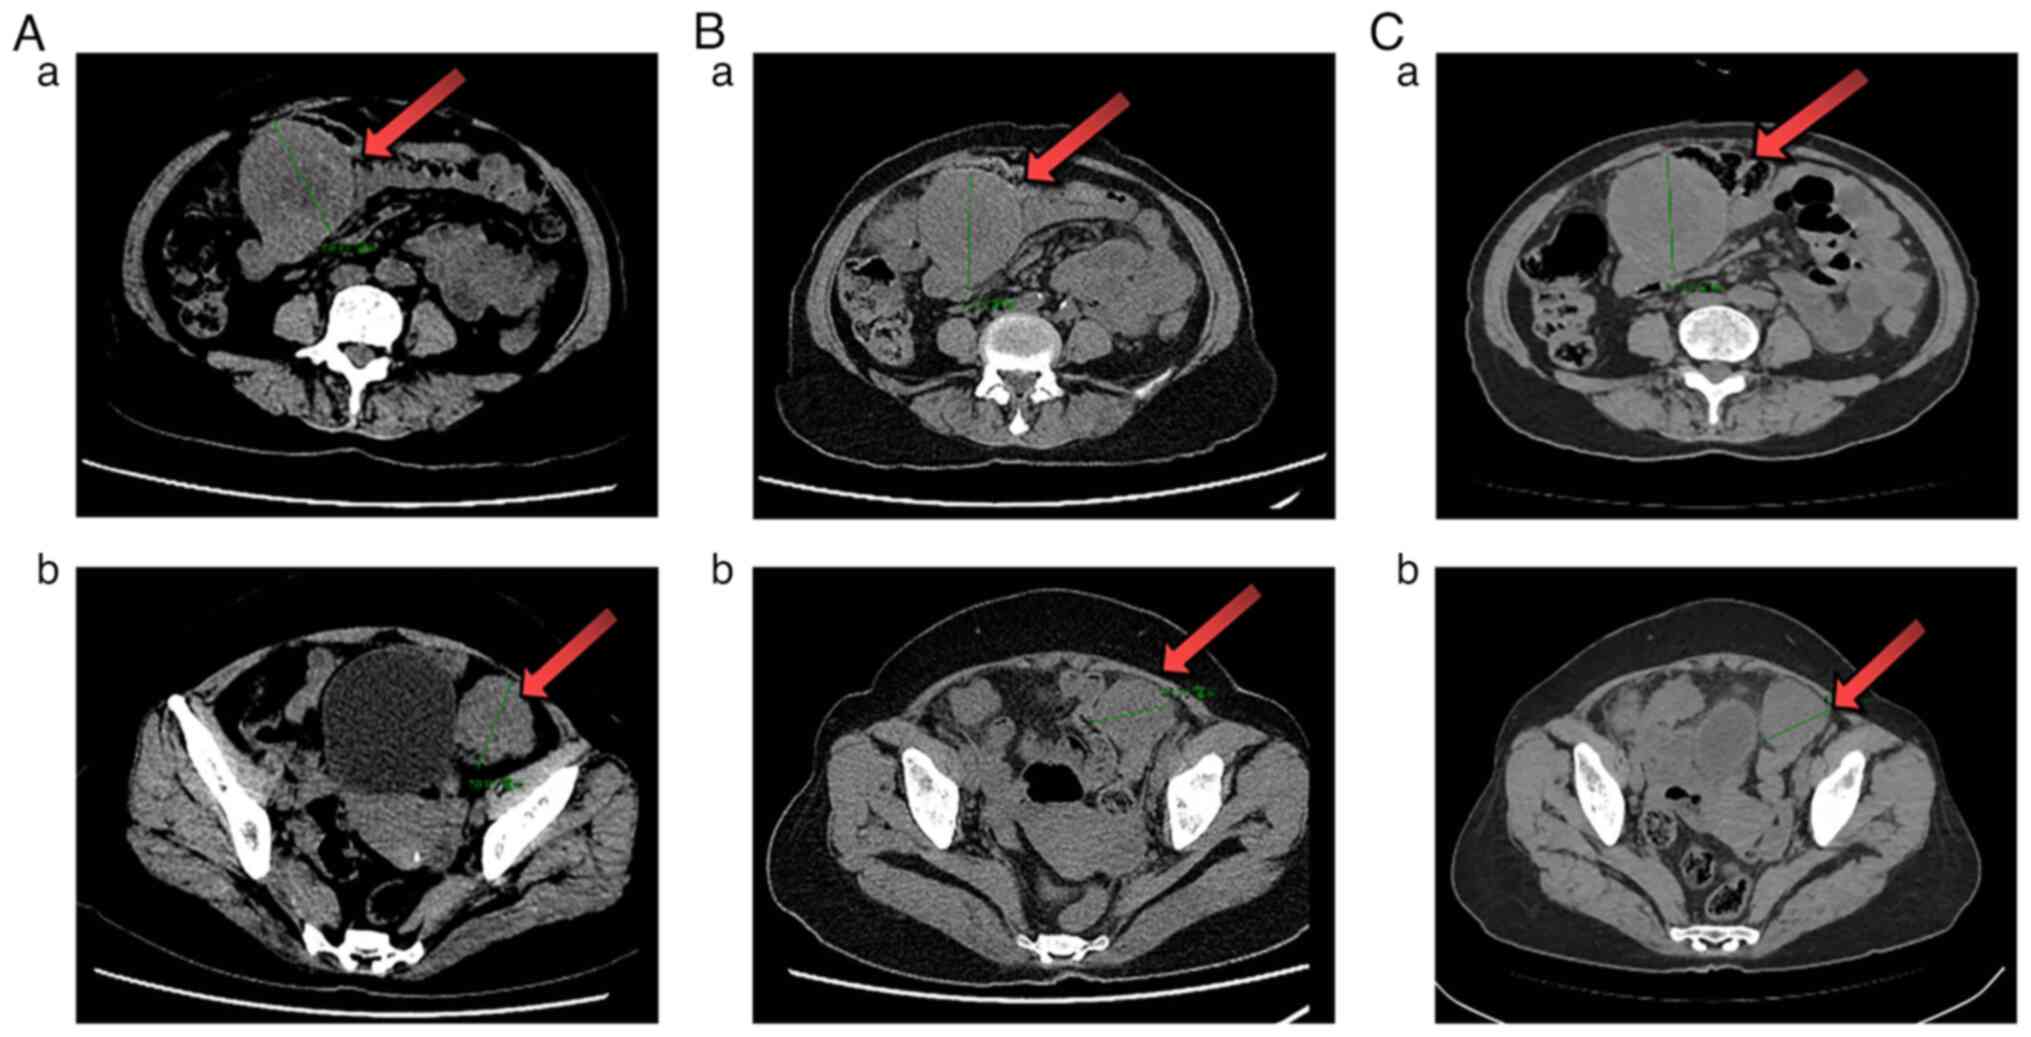

Figure 3.

CT examination after first-line therapy. (A) 11.2 months, (B) 14.2 months and (C) 14.9 months after the first cycle of first-line therapy. (Aa-Ca) Cross-section in peritoneal cavity (green boundaries); (Ab-Cb) cross-section in pelvic cavity. Maximum cross-section diameter of the mass (green boundaries) in the peritoneal cavity (6.9 → 6.2×7.1 → 7.0×7.1 cm). Maximum cross-section diameter of the mass (green boundaries) in pelvic cavity (5.0 → 4.5 → 4.5 cm). The largest masses are also highlighted (red arrows).